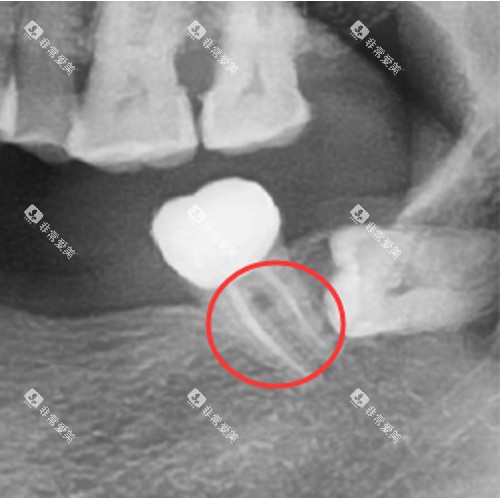

复杂病例需使用CBCT三维影像定位

杭州未来口腔对上颌头一前磨牙(通常为双根管)收费860元,若检测出MB2根管(额外细小根管),需加收500元显微操作费。

杭州亮贝美口腔对下颌头一磨牙(通常4个根管)收费1680元,若检测出5根管异常结构,费用上浮至2400元。